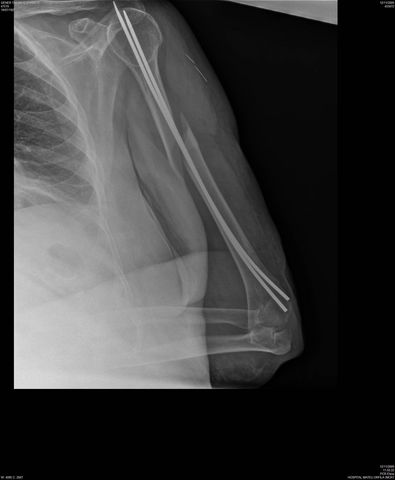

Fractura impactada de húmero .

Fractura de húmero, intensa desviación de fragmentos

Fractura de húmero.

Fractura compleja de húmero.

Fractura de diáfisis de húmero.

Fractura de húmero tras osteosíntesis con clavo gamma.

Fractura subcapital de húmero.